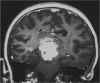

RM:

glioma con segni di trasformazione maligna